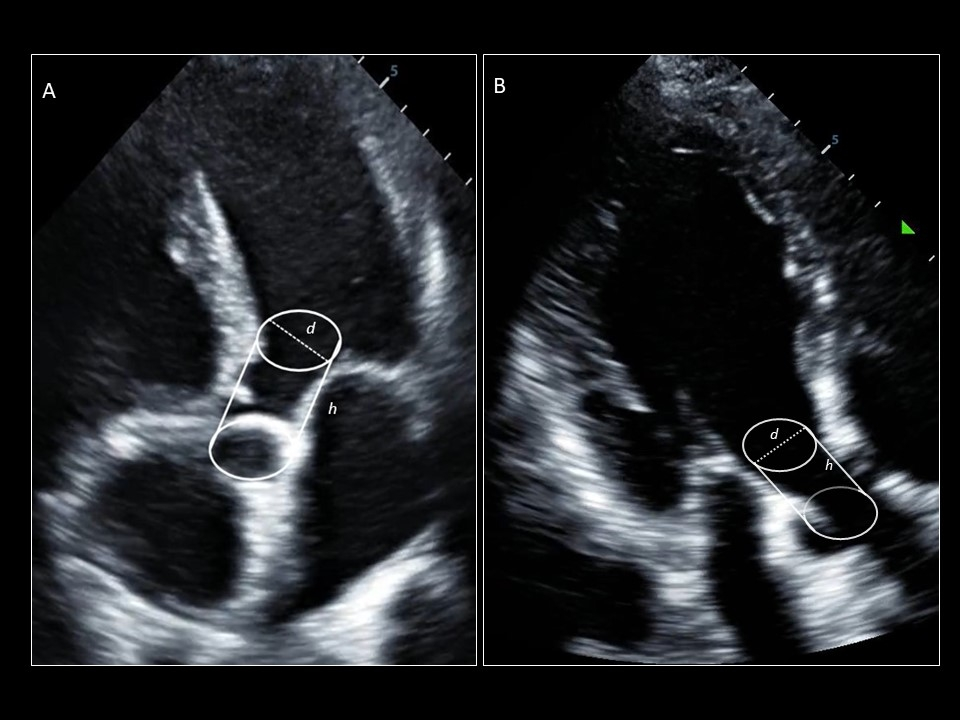

SV = CSA (cm^2) x VTI (cm) = 0.785 x (LVOTd)^2 x (LVOT VTI)

• CO by doppler assumes LVOT is a cylinder but real world it is not